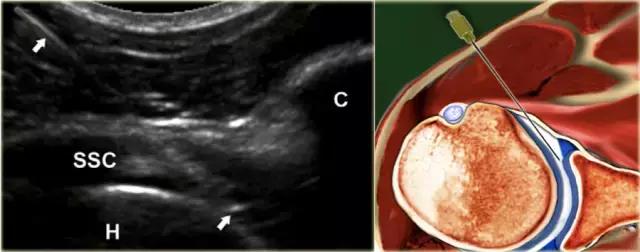

患者仰卧。腿被保持在微小的内旋和外展,从而缓和局部囊结构的紧张和使髂腰肌腱和囊在中心移出预期的针路径。优选地,使用5-3.5MHz的弯曲阵列换能器,其提供必要的穿透深度。通常,针对平均成年人使用长度为9cm的21号针。 在较小的成人或儿童中,可以使用23号5cm皮下注射针。

局部麻醉剂可以在主要注射之前注射,但是这需要额外的操作以及在关节中的非造影流体(麻醉剂)留下较少的空间,使有限的关节空间更小,以及可能的2个穿刺。

可以通过在包含麻醉剂和注射流体(对比剂或药物)的两个注射器之间使用三通连接器,来避免麻醉后换造影剂时引起的以外的脱针。